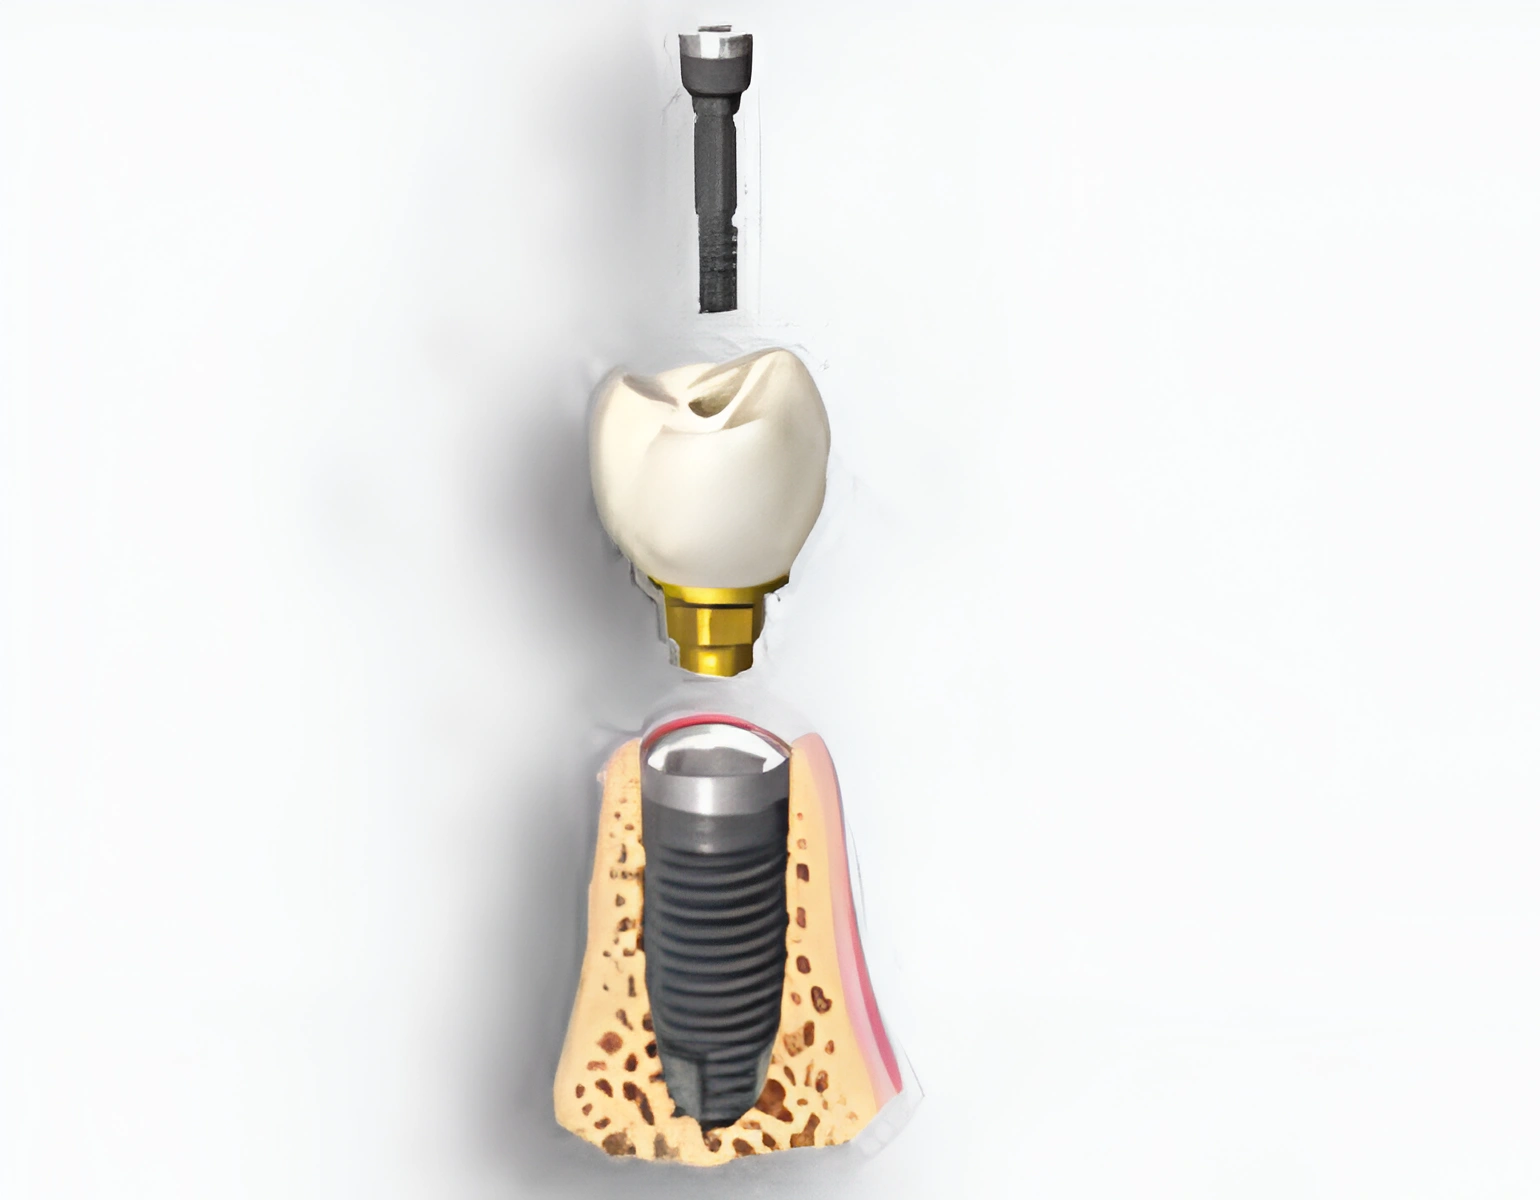

Implant Info Sheet